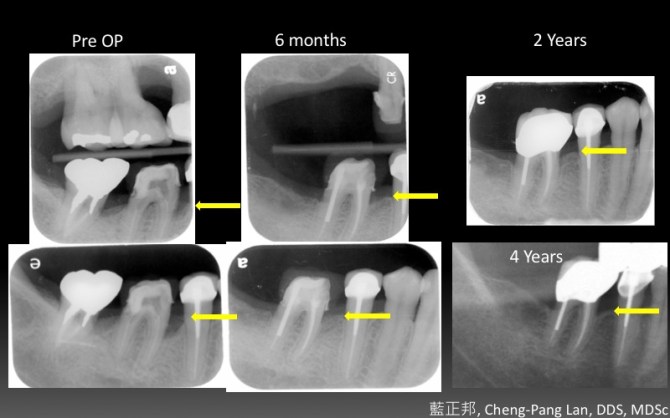

Periodontal Regeneration – Case C